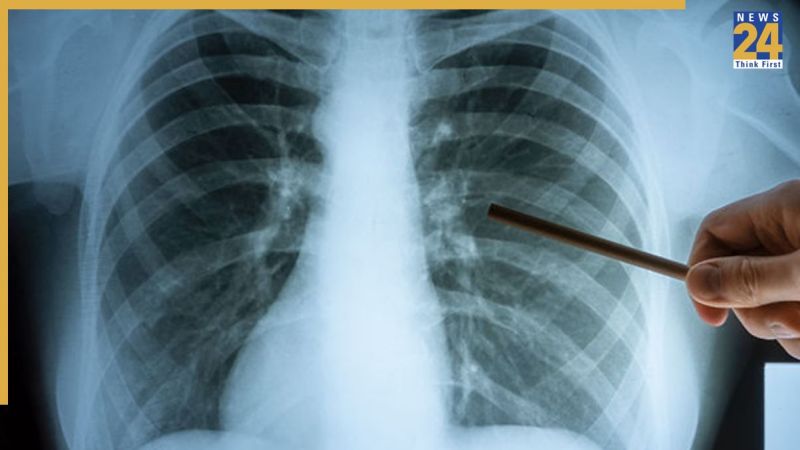

अहमदाबाद शहर से स्वास्थ्य को लेकर सामने आई एक डराने वाली रिपोर्ट .आंकड़ों के मुताबिक, अहमदाबाद में पिछले एक साल में टीबी यानी ट्यूबरक्लोसिस के 15 हजार से ज़्यादा नए मामले दर्ज किए गए हैं.

15,461 मरीजों में से 10,809 मरीज सरकारी अस्पतालों में है जबकि 4652 मरीज निजी अस्पतालों में इलाज करवा रहे हैं

इससे भी ज़्यादा चिंताजनक बात यह है कि इस दौरान 700 लोगों ने इस बीमारी से अपनी जान गंवा दी है.””स्वास्थ्य विभाग की रिपोर्ट बताती है कि वटवा, बहरामपुरा और गोमतीपुर जैसे इलाके टीबी के सबसे बड़े हॉटस्पॉट बनकर उभरे हैं.

एक साल में कुल 1,49,710 संदिग्ध मरीजों की जांच की गई थी जिनमें से 15461 टीवी के मरीज पाए गए.. टीबी मरीजों की हुई 700 में मौत में से 59 फीसदी मौतें रोग का देरी से पता चलने के चलते 30 दिन के भीतर ही हो गई .

ताजा स्थिति के मुताबिक रोजाना टीबी के 42 नए मामले आ रहे हैं और यह जानलेवा रोग रोज दो लोगों की मौत की वजह बन रहा है .विशेषज्ञों का मानना है कि कुपोषण और बीमारी का देरी से पता चलना, मौतों का सबसे मुख्य कारण बन रहा है.

हालांकि सरकार पोषण योजना के तहत मरीजों को आर्थिक और चिकित्सा सहायता दे रही है, लेकिन मौत के बढ़ते आंकड़े बताते हैं कि अभी जागरूकता की और भी ज़रूरत है.